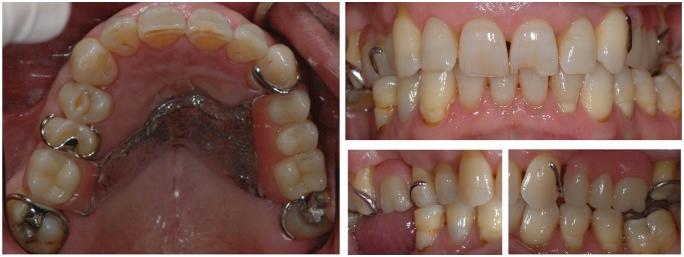

This report describes a clinical and laboratory protocol used in the fabrication of a removable partial dental prosthesis with a digital workflow in a 73-year-old patient. The metal framework was produced with a selective laser melting technique. For quality assurance and discrepancy analysis, the framework was superimposed and compared to the respective digital design file, and the printed model was also compared to the digital impression and rendered as a 3D colour map. Differences were detected in the framework on the clasp of tooth 17 (upper right second molar) and on the printed model on the interproximal surfaces of the abutments, particularly on tooth 17 and palatine area. The use of this digital workflow allowed for the achievement of an removable partial dental prosthesis with a good fit and occlusion with minimal adjustments, with the reduction of both clinical and laboratory time. Further studies are needed to gain a better understanding of these techniques.

本报告描述了一名73岁患者采用数字化工作流程制作可摘局部义齿的临床和实验室方案。金属框架采用选择性激光熔化技术制作。为了进行质量保证和差异分析,将框架进行叠加并与相应的数字设计文件进行比较,同时将打印模型与数字印模进行比较并渲染为三维彩色图。在右上第二磨牙(17号牙)卡环处的框架以及基牙邻面,特别是17号牙和腭部区域的打印模型上检测到差异。这种数字化工作流程的使用使得能够制作出贴合度和咬合良好且调整最少的可摘局部义齿,同时减少了临床和实验室时间。需要进一步研究以更好地理解这些技术。